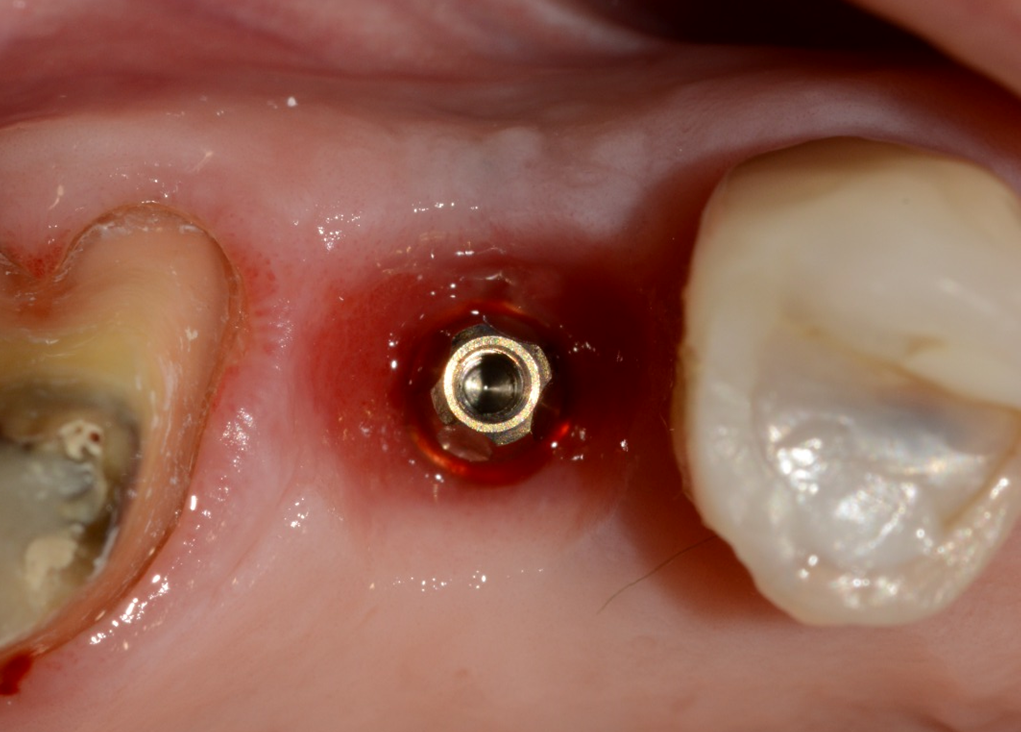

Aguardado o tempo, foi realizada a reabertura do implante com incisão deslocada para a palatal, deixando mais mucosa ceratinizada por vestibular (Figura 12). Foi instalado um Pilar Ideale (Figura 13) e confeccionado um provisório parafusado sobre ele. As suturas acomodaram a mucosa sobre o provisório, conformando-a ao perfil de emergência desejado (Figura 14).

Após 21 dias, a mucosa se apresentava saudável e com um perfil de emergência adequado para a confecção da coroa protética definitiva sobre implante (Figura 15). Foram realizados os procedimentos de moldagem com personalização do transferente para a cópia fiel do perfil de emergência, e uma coroa metalocerâmica foi instalada sobre o Pilar Ideale e a reabilitação foi finalizada (Figura 16).